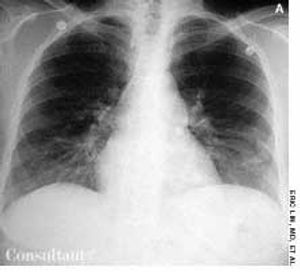

A 47-year-old woman presented to the emergency department with chest pain of sudden onset. The patient had no history of coronary artery disease, peptic ulcer, gastroesophageal reflux disease, or similar episodes of chest pain. She had not traveled long distances or suffered trauma or injury recently.